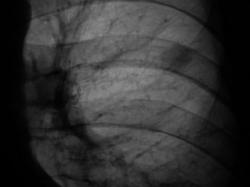

2009 г.

Окружающая легочная ткань - 2008 и 2009 г.

Вердикт диспансера - "наблюдение в динамике".

Кстати, какие-то неясные очажки вокруг. А вдруг туберкулема?